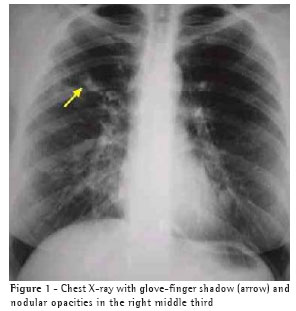

were bilateral and diffuse. Additional examinations showed the following: normal spirometry results, positivity for A. fumigatus in immediate cutaneous reaction allergy testing (skin prick test); eosinophilia (13%) in the blood workup; total serum IgE levels higher than 1000 ng/ml; and radioallergosorbent test (RAST) class 3 in the determination of specific IgE for A. fumigatus. On the chest X-ray, glove-finger shadows were observed in the right superior third (Figure 1). The high-resolution computed tomography scan revealed central bronchiectasis (Figure 2).

In various studies, the changes observed on the chest X-rays of patients with ABPA have been described as extensive consolidations and alveolar infiltrate, predominantly occurring in the superior lobes, together with mucoid impaction in the central bronchus. The findings known as the glove-finger shadow and the toothpaste shadow are transitory images of mucoid impaction, which can disappear with cough or after corticosteroid administration.(7-9) On the chest X-ray, opaque shadows in glove-finger form were observed in the upper third of the right hemithorax (Figure 1). On the high-resolution computed tomography scan, there were signs of central bronchiectasis (Figure 2). According to the literature, glove-finger shadows are suggestive of ABPA,(10) reflecting inflammation, thickening, and dilation of the bronchial tree caused by the mucoid impaction in the airways.(11) In order to , It has been suggested that high-resolution computed tomography is the best diagnostic technique for detecting central bronchiectasis, for which chest X-ray is neither sensitive nor specific.(4)